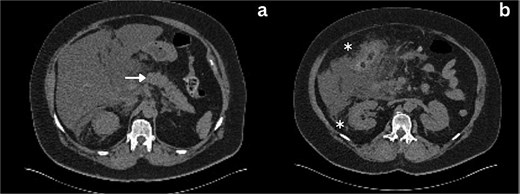

Following a brief clinical response to the initial conservative management for 24 hours, the patient started deteriorating and developed generalized peritonitis with worsening of inflammatory markers (C-reactive protein escalated to 438 mg/l). Consequently, she underwent an emergency diagnostic laparoscopy as the cause of peritonitis was not clear. Intraoperatively, it was observed that there was free bile in the peritoneal cavity, more so around the liver and the right paracolic gutter. There was also a bile collection behind the right colon and hepatic flexure of the colon, raising the possibility of a retroperitoneal source. The hepatic flexure of the colon was mobilized to assess the source of the leak. No obvious ongoing leak was noticed. As a precautionary measure, an Upper GI endoscopy was conducted intra-operatively to rule out any gastroduodenal perforation, as no obvious source of bile leak was seen from the biliary tree. This revealed the presence of bile in the stomach and confirmed normal anatomy up to the third part of the duodenum. The remaining intra-abdominal organs appeared unremarkable. Thorough peritoneal lavage was given, and 22 Fr abdominal drains were placed in the subhepatic, para-hepatic space, and pelvis, respectively, as the source of leak was not found. The following day, an endoscopic retrograde cholangiopancreatography (ERCP) was performed, which identified a small leak around the area of the cystic duct stump (Fig. 3). In response, a 5 cm-sized 7 Fr double pigtail stent was inserted into the CBD. A post-ERCP CT scan was performed to evaluate the contrast leak. The CT imaging revealed an extraluminal contrast leak originating from a defect in the posterior CBD (Fig. 4). Notably, the cystic duct stump remained intact and anterior, establishing the diagnosis of Spontaneous biliary leak from the CBD.

ERCP imaging reveals contrast leak in the cystic duct stump region.